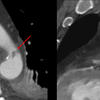

Min Aortic Injury

MAI